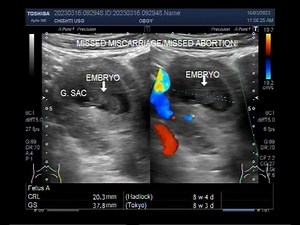

Early Missed miscarriage of about 8 weeks.

8.3K views

Mar 20, 2023

YouTube

Saeed Ahmad

Ultrasound Video showing a case of missed miscarriage of about 7 to

…

157.1K views

Nov 1, 2017